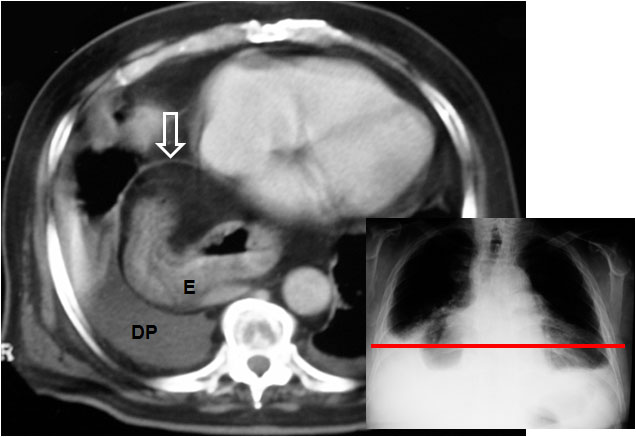

Signo de rotura diafragmática en TC, que consiste en la ausencia de un segmento del diafragma en uno o más cortes. La imágenes corresponden a un paciente con rotura traumática del hemidiafragma izquierdo. En la secuencia de cortes en la zona de transición toraco-abdominal no se ve el hemidiafragma izquierdo en ningún momento. Flecha roja: ángulo esplénico del colon herniado. Flecha blanca: estómago herniado con nivel hidroaéreo. Flecha verdenegra: bazo.

Otro ejemplo de diafragma ausente, esta vez en el lado derecho. Se trata de un paciente con traumatismo toracoabdominal. La radiografía de tórax muestra un cortorno alterado del hemidiafragma derecho. En la imagen puede verse parte del diafragma (línea marcada con la flecha blanca) en una posición anómala. Sin embargo, el diafragma no es visible entre el estómago herniado (E) y el derrame pleural derecho (DP).